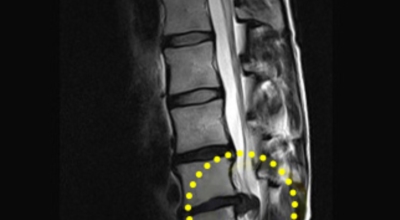

디스크는 일어선 상태에서는 중력을 받아 납작해져서 바깥쪽으로 약간 볼록한 형태가 된다고 합니다. 디스크는 그 특수한 구조 때문에 웬만한 힘이 가해져도 효율적으로 쿠션 역할을 할 수 있겠습니다. 그러나 급작스럽게 무거운 물건을 들어 올리거나, 부자연스러운 자세를 오랜 시간 취하면 디스크에 무리한 힘이 가해지면서 디스크가 밖으로 돌출이 되게 돼요. 심한 경우 디스크를 감싼 막이 터지면서 그 안에 있는 수핵이 튀어나오게 돼요.

디스크는 대개 후방이나 후외방으로 돌출되는데 이때 바로 곁에 있는 신경을 누르게 된다고 합니다. 돌출된 디스크는 척추의 어느 부위에나 일어날 수 있어요. 목에 생기면 '목 디스크', 등에 생기면 '등 디스크', 허리에 생기면 '허리 디스크'라고 부른다고 합니다.

이와 같이 디스크가 돌출되어 신경을 눌러 요통 또는 다리가 아프고 저린 증상을 유발하는 병을 '추간판 탈출증' 및 '디스크 탈출증'이라고도 불러요. 발생 빈도별로 보면 허리 디스크가 가장 흔합니다. 그다음이 목 디스크이지요. 등 디스크는 드문 병이라고 합니다.